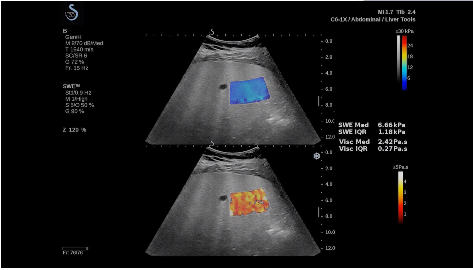

法國(guó)聲科影像(SuperSonic Imagine,SSI. Euroniex:FR0010526814)近日發(fā)表公告,宣布其研發(fā)的新一代“極速”超聲成像平臺(tái)(UltraFast Imaging),首次實(shí)現(xiàn)了肝臟的多項(xiàng)超聲定量評(píng)估新指標(biāo)同步檢測(cè),包括:Att PLUS,SSp PLUS和Vi PLUS等,基本涵蓋肝臟相關(guān)病理變化指征的如纖維化、脂肪變、炎癥等。據(jù)悉,此多項(xiàng)新技術(shù)新將搭載于新Aixplorer系列E超系統(tǒng)。

法國(guó)聲科影像公司(SuperSonic Imagine. SA,F(xiàn)rance),2005年由三位諾貝爾獎(jiǎng)級(jí)科學(xué)家主導(dǎo)創(chuàng)立,專注于E超的開(kāi)發(fā)和生產(chǎn),是目前世界上唯一可以同時(shí)應(yīng)用兩種波進(jìn)行人體檢測(cè)的系統(tǒng):縱波形成高質(zhì)量的二維組織結(jié)構(gòu)圖像,而橫波可以使醫(yī)生實(shí)時(shí)準(zhǔn)確地看到并分析組織的硬度,有效減少有創(chuàng)檢查、避免損傷。

E超相關(guān)技術(shù)已被多項(xiàng)多中心大樣本研究證實(shí)對(duì)于肝纖維化無(wú)創(chuàng)評(píng)估有重要意義,同時(shí)也可全面應(yīng)用于乳腺、甲狀腺、肝臟、前列腺、肌骨、婦科等全身各組織器官的定量評(píng)估和鑒別診斷。在慢性肝臟方面,聲科E超的肝臟相關(guān)定量診斷技術(shù)集,于2018年獲得美國(guó)FDA認(rèn)證,成為FDA歷史上首次獲批的單病種超聲全面定量解決方案。

E超是在原有B超、彩超(彩色多普勒CDFI)基礎(chǔ)上研發(fā)成功的新一代超聲剪切波彈性成像系統(tǒng),是一種能夠全面應(yīng)用于表淺組織、腹部臟器,血管等方面的組織彈性成像技術(shù)。根據(jù)組織硬度彈性值的不同,有效鑒別實(shí)性腫瘤的良惡性。對(duì)于惡性病變的診斷具有較高的特異性和敏感性,尤其對(duì)于甲狀腺、乳腺、前列腺等小器官,能夠完成常規(guī)超聲不能完成的組織定量分析,可以實(shí)時(shí)、全幅、全定量獲得組織彈性(硬度)信息,為鑒別腫瘤的良惡性提供客觀、量化的診斷依據(jù)。